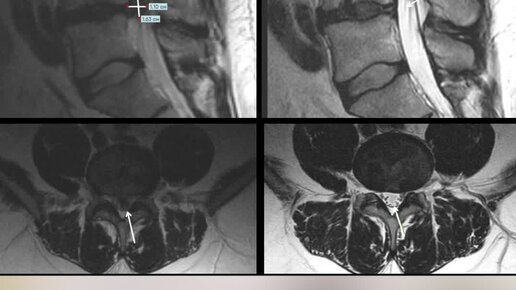

Результаты лечения крупной межпозвонковой грыжи в нашем центре